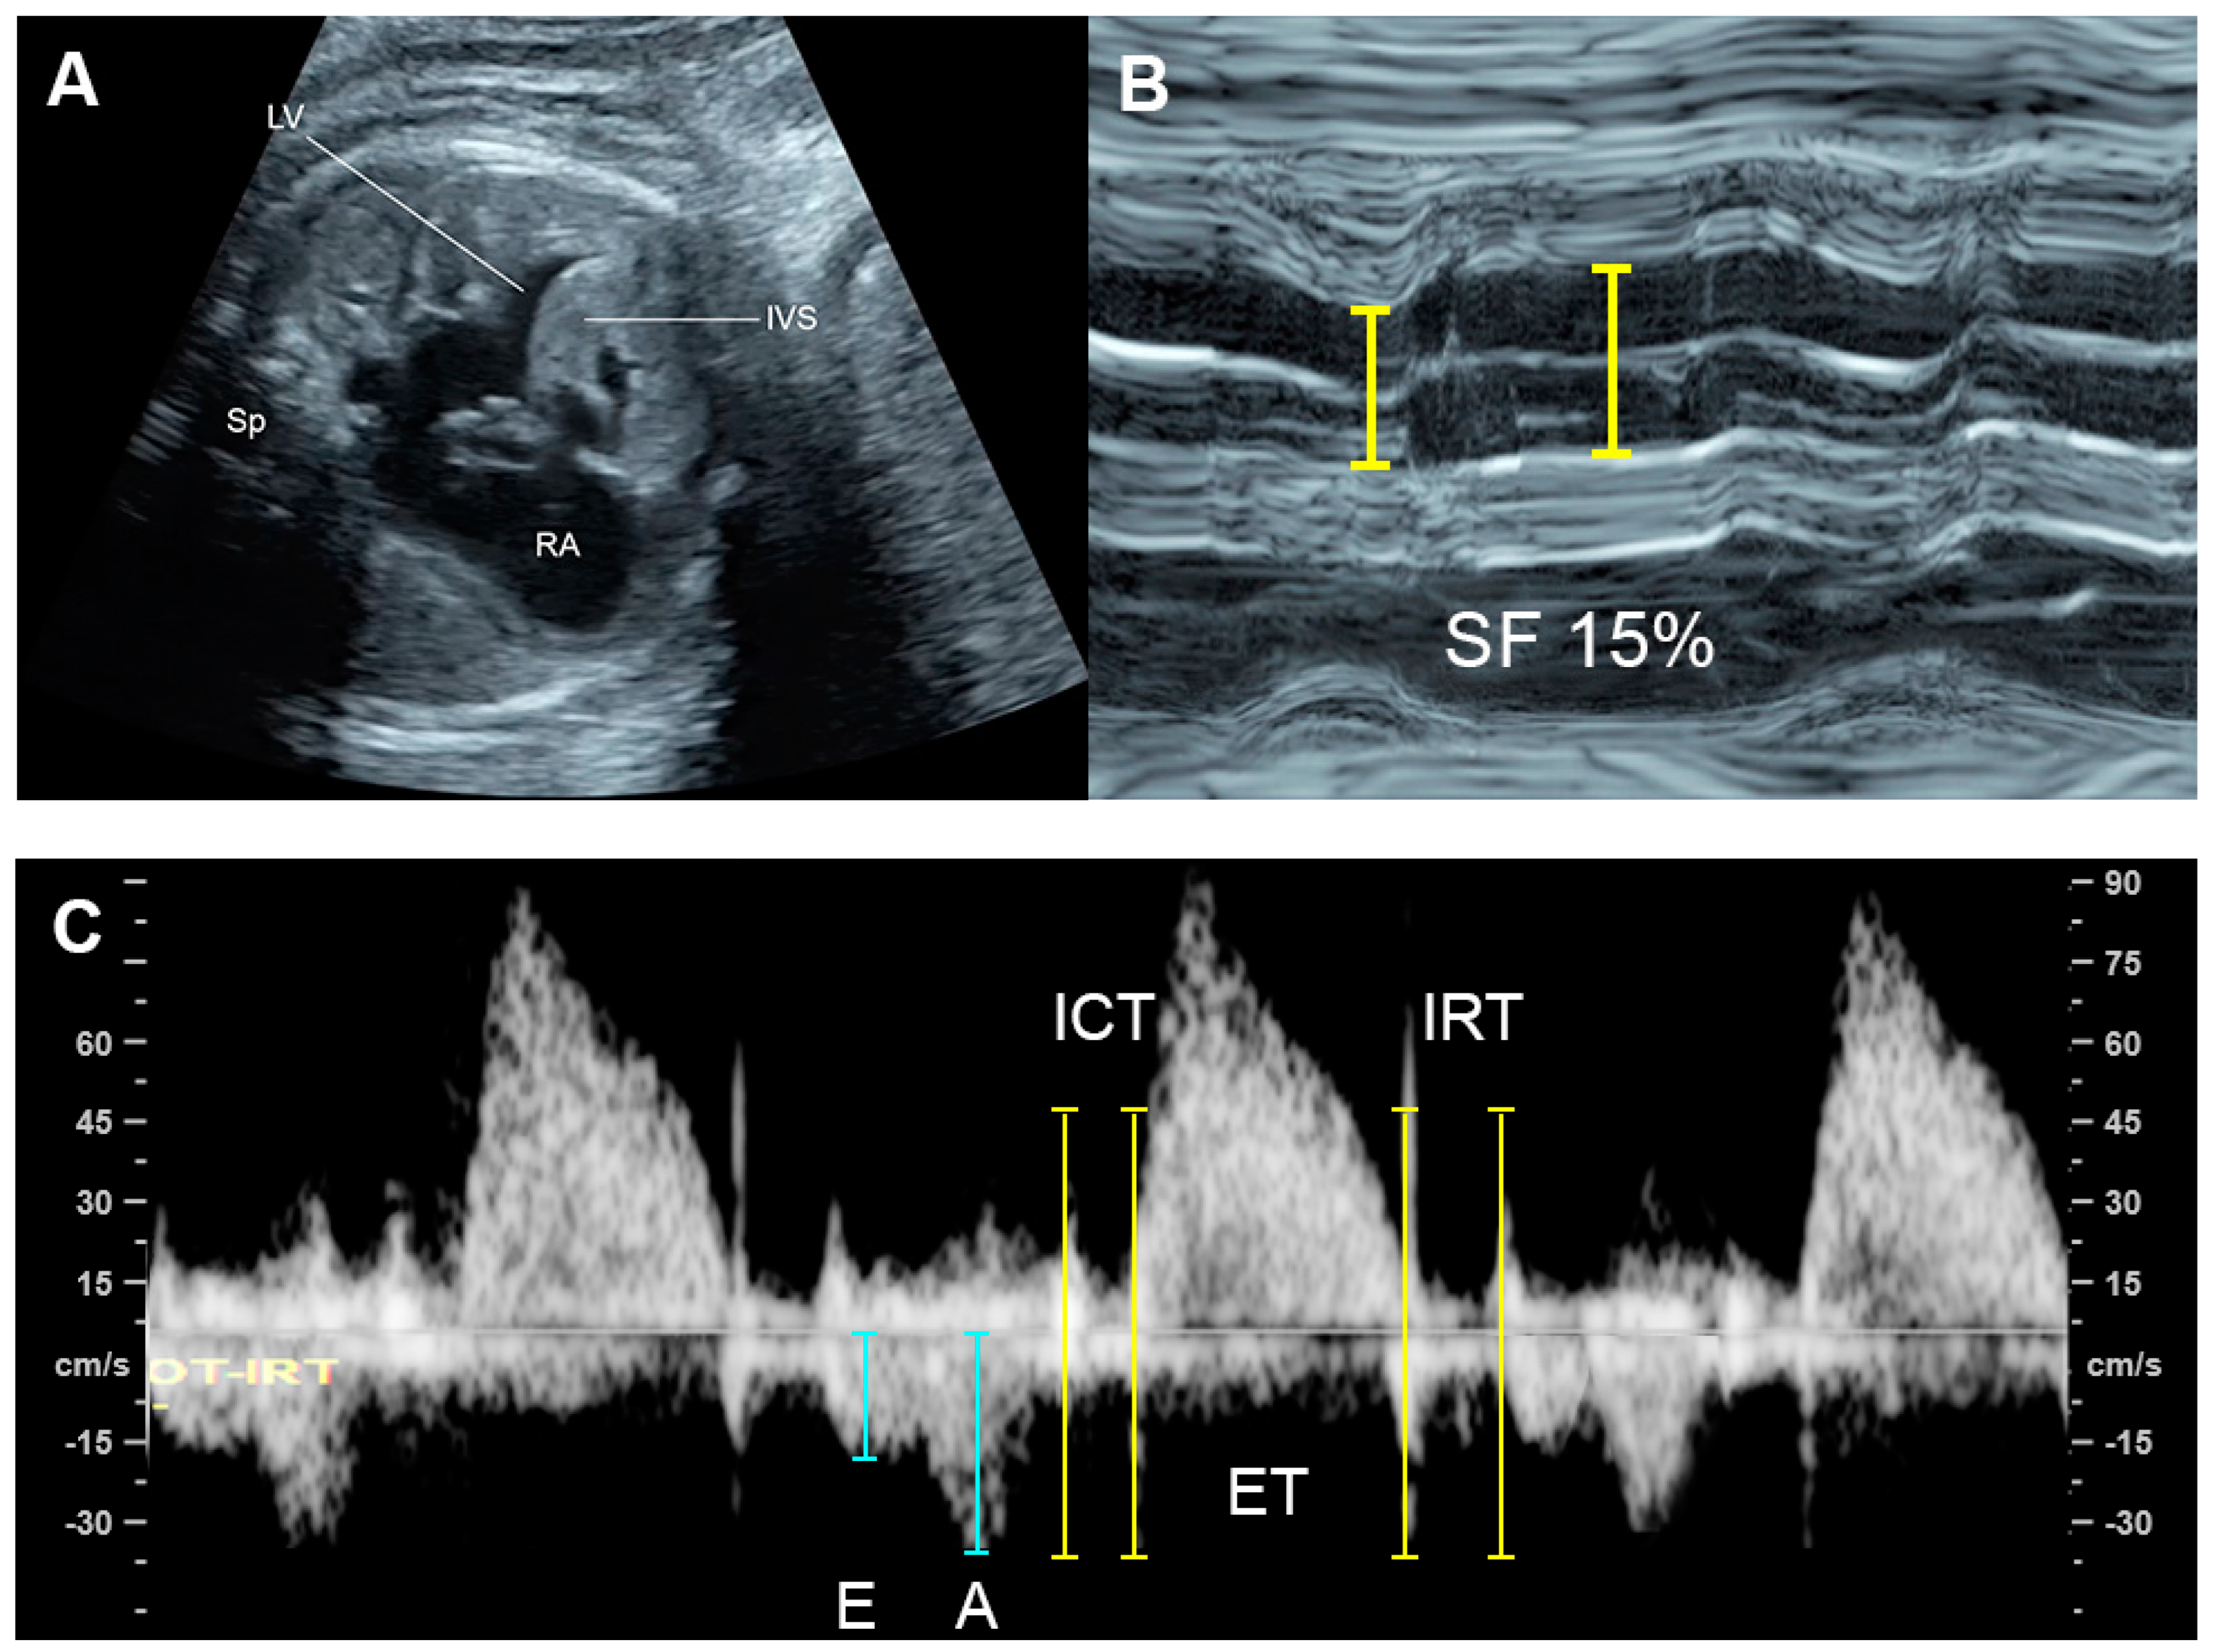

| Parameters | Abnormal Changes | Interpretation |

|---|---|---|

| Dimension | ||

| Cardiothoracic area ratio | Increased >35% | Cardiac enlargement |

| Cardiothoracic diameter ratio | Increased >95th centile | Cardiac enlargement |

| Inflow characteristics | ||

| Filling time fraction | Decreased | Diastolic dysfunction |

| E/A ratio | Monophasic | Diastolic dysfunction |

| Decreased | Diastolic dysfunction | |

| Increased | Volume loading/External compression | |

| Venous PW Doppler | ||

| Inferior vena cava | Reversed A-wave >20 cm/s | Diastolic dysfunction /increased venous pressure |

| Decreased S-wave | Tricuspid regurgitation | |

| Ductus venosus | Absent or reversed A-wave | Diastolic dysfunction/increased venous pressure |

| Performance | ||

| Shortening fraction | Decreased (<28%) | Systolic dysfunction |

| Increased | Reduced afterload/increased contractility | |

| Ejection fraction | Decreased <50%) | Systolic dysfunction |

| Cardiac output (Stroke volume) | Decreased (Z < −2) | Systolic dysfunction/poor filling |

| Increased (Z > +2) | Reduced afterload/volume load | |

| Tei index | Increased > 0.50 | Global cardiac dysfunction |

| ICT: 28 (22–33) ms | Prolonged | Systolic dysfunction |

| IRT: 34 (26-41) ms | Prolonged | Diastolic dysfunction |

| Systolic strain/Strain rate | Increased | Reduced afterload |

| Decreased | Reduced contractility | |

| E/Vp (Color M-mode) | Increased | Diastolic dysfunction |